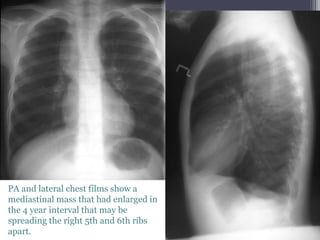

PA and lateral chest films show a

mediastinal mass that had enlarged in

the 4 year interval that may be

spreading the right 5th and 6th ribs

apart.

โ€ข An enhanced chest CT exam shows a homogeneous mass, of fatty density,

with a few septations, in the right posterior mediastinum causing some

anterior displacement of the right main stem bronchus.

โ€ข Dx:Lipoma, Posterior Mediastinal